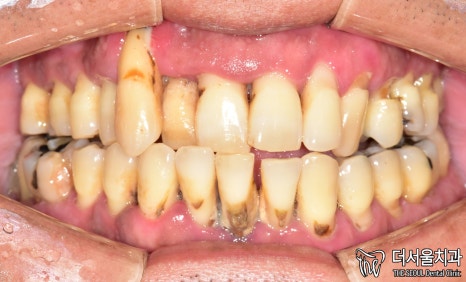

1. 첫 진료

먼저 사진을 보겠습니다.

여러분이 보더라도

구강 상태가 심각하다는 걸 알 수 있습니다.

올바른 교합이 이뤄질 수 없을 뿐더러

치경부 마모증에 쌓여있는 치석에 충치까지

손댈 부분이 너무 많네요.

게다가 구취까지 나고 있었기에

걱정되는 상황이었습니다.